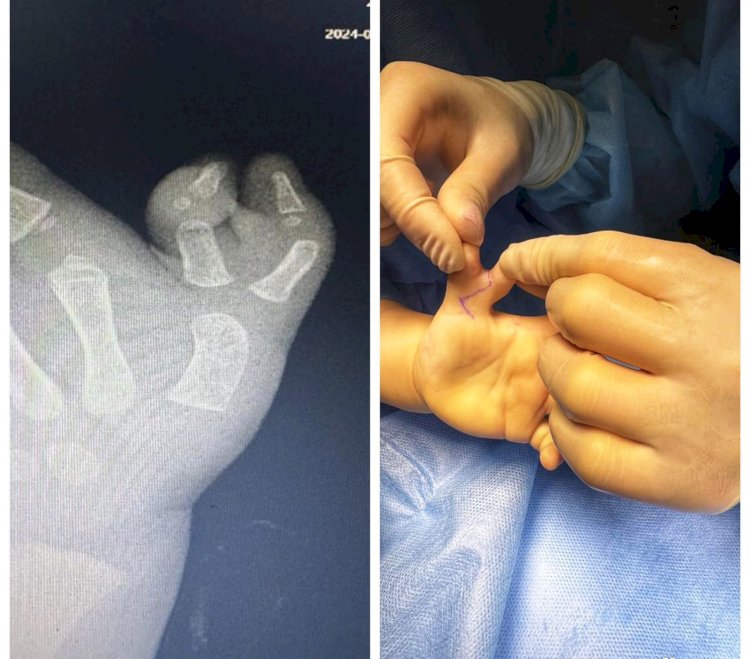

Дәрігерлер  екі жасар сәбидің  артық саусағын алып тастады

Оңтүстік астанадағы №2 Қалалық клиникалық балалар ауруханасының ортохирургтері Ресейдің Н.Пирогов атындағы Жоғары медициналық технологиялар клиникасы мамандарымен бірлескен шеберлік класы аясында...

01.02.2024 04:44 • 1,422 көру